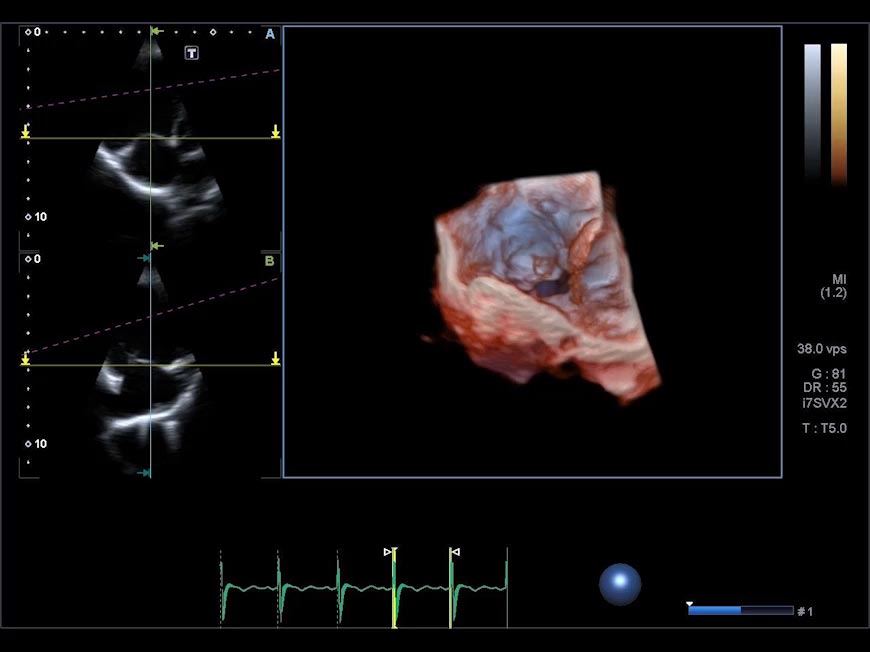

Small compact, lightweight design.

Pediatric Cardiac Volume Matrix Transducer* (i7SVX2)

- Matrix array

- Single crystal

- Small compact, lightweight design

- Advanced volume features

- Sector and volume sector

- Freq: 2.2-6.0 MHz

- Application: 3D Cardiac (pediatric heart)

*Available on the Aplio i900 only.

Pediatric Cardiac Volume Matrix Transducer Demo Visual assessment of the leaflets

Visual assessment of the leaflets